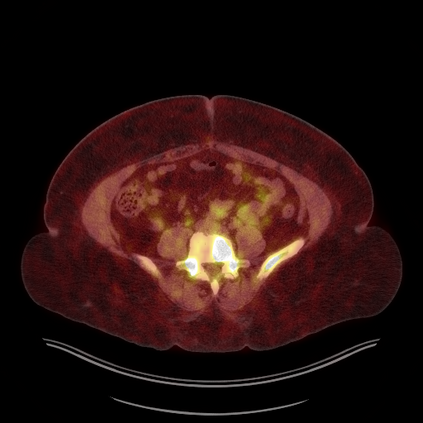

Medical images play a crucial role in assisting diagnosis, remote consultation, and academic research. However, during the transmission and sharing process, they face serious risks of copyright ownership and content tampering. Therefore, protecting medical images is of great importance. As an effective means of image copyright protection, zero-watermarking technology focuses on constructing watermarks without modifying the original carrier by extracting its stable features, which provides an ideal approach for protecting medical images. This paper aims to propose a fragile zero-watermarking model based on dual quaternion matrix decomposition, which utilizes the operational relationship between the standard part and the dual part of dual quaternions to correlate the original carrier image with the watermark image, and generates zero-watermarking information based on the characteristics of dual quaternion matrix decomposition, ultimately achieving copyright protection and content tampering detection for medical images.